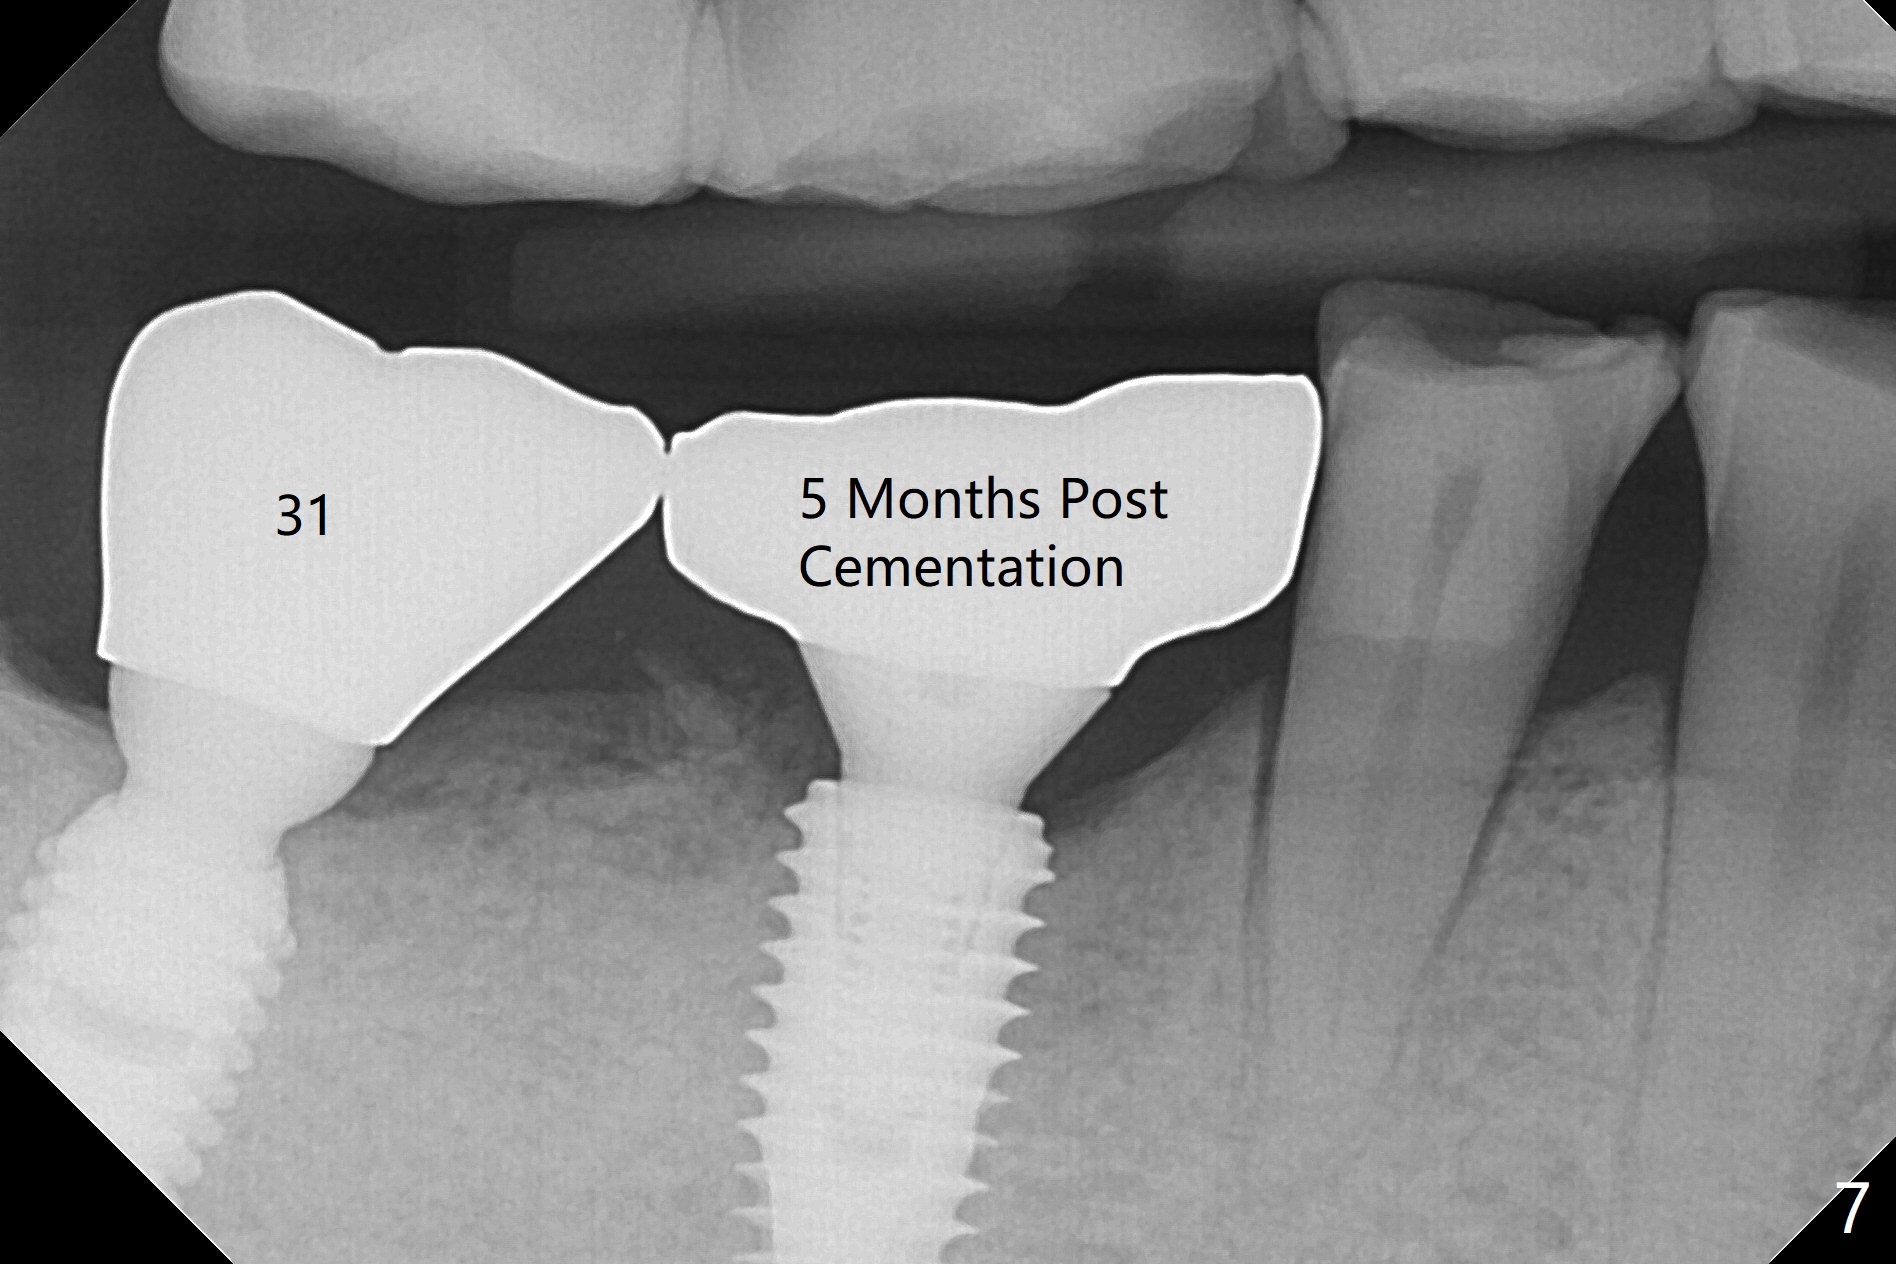

Vertical fracture of the mesial root of the tooth #30 after RCT is associated with bone loss (Fig.00 *). When the mesial portion of the mesial root (M', loose one) is exfoliated, the bone loss resolves (Fig.0). To reduce heat-induced bone necrosis at #19, osteotomy is conducted slowly with copious irrigation with cold saline. Bone density is felt while a 5x10 mm implant is being placed after using cortical tap to the 2nd line of the implant driver. The implant needs to be reverse torqued several times before reaching its final depth (Fig.1 (~50 Ncm)). Since the residual roots are superficially positioned, the immediate implant looks as a delayed one. Although the implant is placed mesial to the septum clinically, its position in X-ray seems to be normal. Because of severe wear and lack of vertical height, a 6.8x5 mm healing abutment is placed. Retention of bone graft (Fig.1 *) is maintained by spreading setting acrylic into the edentulous undercut areas (Fig.2 *). The so called "acrylic dressing" remains in place 3 weeks postop (Fig.8). When it is removed with the healing abutment, the wound heals (Fig.3). Note the limited vertical height. The bone graft placed in the distal socket appears to have been converted to the native bone 3.5 months postop (Fig.4). To reduce severe wear of the natural teeth, the occlusion of the new crown is not heavily decreased (Fig.5). It should be alright considering favorable crown/implant ratio (Fig.6). There is no bone loss 5 months post cementation, although the abutment screw is just retightened (Fig.7). In spite of poor trajectory associated with #18 (Fig.8) and 31 (Fig.7) Bicon implants, the abutments have not been dislodged. For the bruxer, the next implant at #19 with distal root fracture (Fig.8 ^) should be Bicon. The patient complains of food impaction nearly 1 year post cementation. The mesial and distal contacts of #30 crowns are light. When the abutment/crown is removed, there is implant well contamination (food debris). It appears that the previous abutment (5.7x4(2) mm, Fig.6,7) is incompletely seated. When a smaller abutment is placed and torqued at 30 Ncm, it is seated fully (Fig.9 (<: no gap)). New impression is taken. The distal gingival embrasure is larger than the mesial one because of the higher distal crest (Fig.6,7). If there is food impaction distal to the new crown, the distal crestal bone should be removed with lab closure of the embrasure.